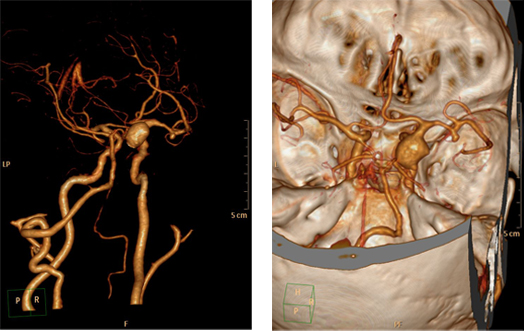

原来是徐老在6月初无明突然觉得自己头痛,恶心呕吐,家人急忙送至当地医院就诊,查头颅CT示:蛛网膜下腔出血。进一步行头颅CTA检查示:右侧颈内动脉大型动脉瘤,右侧大脑中M1段动脉瘤;这可把一家人给急坏了,经过急诊治疗后,徐老还是无明显好转,为求进一步处理,家属带其转院至广东三九脑科医院神经外七科,外七科门诊拟“颅内多发动脉瘤”收入科室。医生详细了解徐老的病情后发现,他既往有高血压病史10年余,未规律服药,血压控制不稳定。查体:神志清,遵瞩活动,对答切题,双侧瞳孔等大等圆,直径2.5mm,对光反射灵敏,伸舌居中,颈亢3横指。

入院后完善术前检查,神经外七科吾太华主任带领团队对病情进行讨论分析,制定好手术方案,于2016年6月7日在全麻下行颅内多发动脉瘤夹闭术,手术取右侧额颞翼点入路,术中见颈内动脉粥样硬化,颈内动脉瘤大型动脉瘤,宽基底,夹闭动脉瘤;然后暴露右侧颈内动脉大型动脉瘤,动脉瘤体约1.5*30px,瘤颈20px,夹闭动脉瘤。术中荧光造影检查动脉瘤不显影,TCD检查夹闭前及夹闭后大致同前。手术过程顺利,术后予以抗炎、营养神经、预防癫痫、止血、护胃、补液、解痉等处理,注意维持“三高”治疗方案。

吾主任术后点评:颅内存在两个或两个以上的动脉瘤,称为多发动脉瘤,无论诊断及治疗都要难于单发动脉瘤,与单一动脉瘤相比,处理多发动脉瘤首先应明确哪个是导致出血的责任动脉瘤,破裂动脉瘤出血再次出血机会更多,如果对责任病灶判断错误,术后发生再出血概率高。此例病人为右侧颈内动脉及右侧大脑中M1段动脉瘤,依据头颅CT蛛网膜下腔出血范围及聚集部位判断右侧大脑中M1段为责任动脉瘤,右侧颈内动脉瘤直径大于50px,大型动脉瘤;手术从右侧翼点入路,首先分离侧裂处理大脑中的责任动脉瘤,需注意保护豆纹动脉,然后处理颈内动脉大型动脉瘤,需保护脉络膜前动脉、后交通动脉,后方注意保护动眼神经,避免术后偏瘫、偏身障碍、眼睑下垂等症状;术后病人取得良好的效果,一次开颅夹闭两个颅内动脉瘤,手术损伤小,患者恢复快,术后12天办理出院,肢体功能良好。术后复查头颅CTA检查动脉瘤不显影,远端血管显影良好。

术前CTA